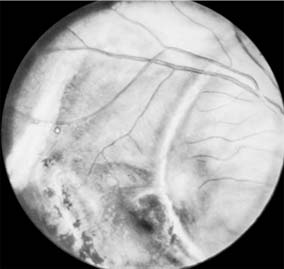

In addition to rupture of the scleral wall, contusive forces to the eyeball can result in motility disorders, subconjunctival hemorrhage, corneal edema, iritis, hyphema, angle-recession glaucoma, traumatic mydriasis, rupture of the iris sphincter, iridodialysis, paralysis of accommodation, lens dislocation, and cataract. Injuries sustained by posterior structures include vitreal and retinal hemorrhages, retinal edema (commotio retinae, or Berlin's edema), retinal holes, vitreous base avulsions, retinal detachment, choroidal rupture, and optic nerve contusion or avulsion (Figures 19-3 and 19-4).

Figure 19-3

Figure 19-3: Hole in retina, macular area, posttraumatic.

Figure 19-4

Figure 19-4: Choroidal ruptures. (Photo by Diane Beeston.)